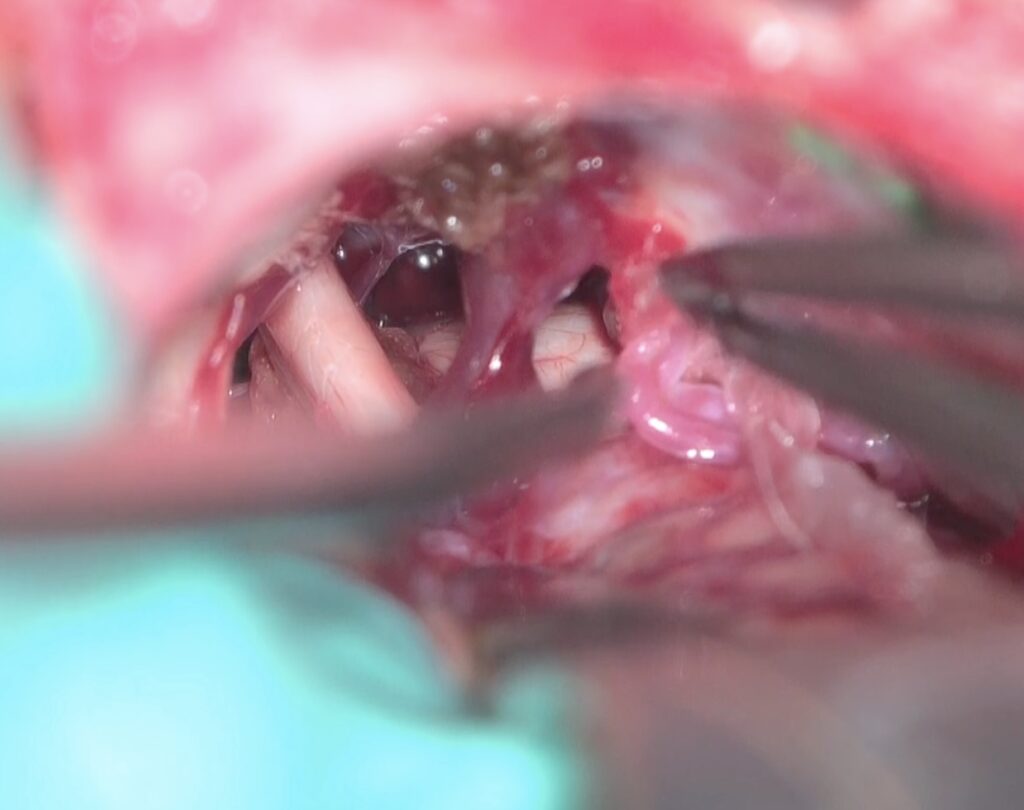

左三叉神経痛の手術をしました。カルバマゼピンで抑えられい強い痛みがありましたが、手術後痛みが完全になくなり食事も取れるようになりました。 2025 12/05 顔面痙攣・三叉神経痛 2025年12月5日ScreenshotScreenshotScreenshotScreenshotScreenshot 顔面痙攣・三叉神経痛 よかったらシェアしてね! URLをコピーしました! URLをコピーしました! 2025/9月 左聴神経腫瘍の手術をしました。術後顔面神経麻痺が出現しましたが2ヶ月程度で回復しました。 250910 西嶋久勝 高浜新町長にお会いしました。 この記事を書いた人 kikuta 関連記事 2603月 67歳男性の右顔面痙攣を手術しました。 2026年3月22日 2603月 58歳女性の左顔面痙攣を治療しました。VAとAICAの複合型圧迫でしたがうまく治癒できました。 2026年3月21日 46歳男性、開眼できないほどのVA型左顔面痙攣を手術しました。術後まだ完全には消失していませんが痙攣は著明に軽減しました。 2026年3月3日 19歳女性の三叉神経痛を手術しました。術後痛みは消失した様子です。 2026年3月3日 87歳女性、繰り返しブロックを行いガンマナイフも行った、難治生三叉神経痛を手術しました。高齢ですが無事一発治癒しました。 2025年12月11日 2025年8月 78歳 VA型の顔面痙攣の神経減圧術を行いました。M-TEPを併用し無事治癒しました 2025年12月4日 2025年5月 テグレトールで治らない左三叉神経痛の手術を行い直後より痛みは消失しました。 2025年9月25日 畑山式MVDハンズオンセミナーに東野先生と参加してきました 2025年3月22日